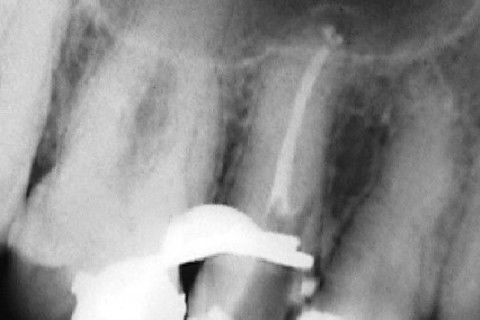

Calcificação Distrófica